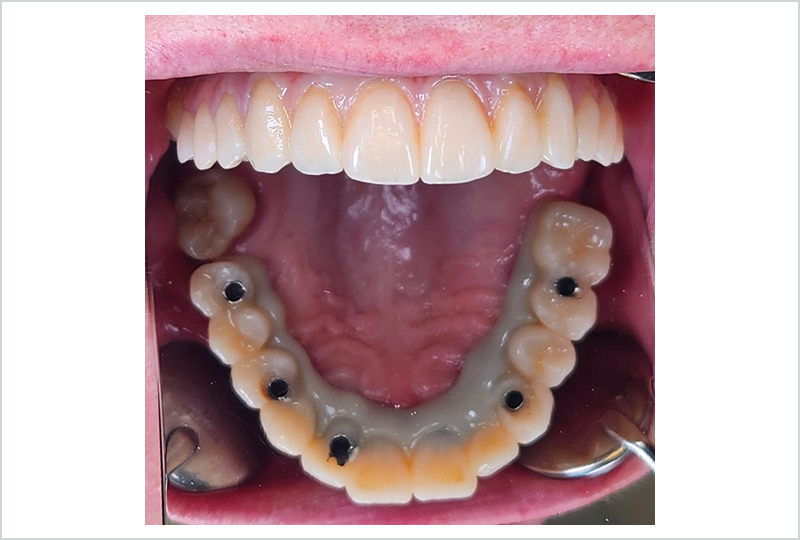

ODT Giovanni Rossi: Il paziente ci è ben noto, è una nostra conoscenza recente ma importante. Con lui abbiamo intrapreso un percorso di pianificazione chirurgica, riabilitato in carico immediato con una protesi stampata e caratterizzata nei toni rosa in composito.

Dopo alcuni mesi abbiamo finalmente raggiunto la completa maturazione dei tessuti e la perfetta integrazione degli impianti. Il paziente è soddisfatto del suo provvisorio, tanto da chiedere più volte: "Perché non lasciamo questa protesi? È perfetta!" (Figure 1, 2).

Fig. 2

Effettivamente, il provvisorio è molto piacevole. Le resine da stampa 3D e i moderni compositi stanno cambiando il nostro approccio alla produzione dei dispositivi protesici, ma avevamo bisogno di una sottostruttura che garantisse una durata adeguata per la protesi, mirata a sopravvivere oltre i 15-20 anni della vite utile di un impianto dentale.